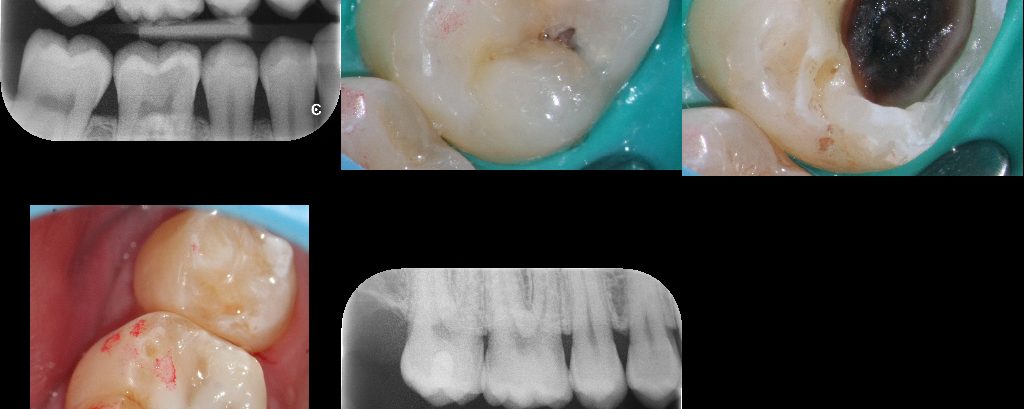

Selective Caries Removal

June 25, 2018 13 comments

Selective Caries Removal (SCR) is a paradigm shift from traditional views on the treatment of caries (i.e. all caries needs to be removed). In most situations I subscribe to the traditional view but there are situations where removing all the caries will necessitate complete RCT which may not be feasible (e.g. the very young and […]